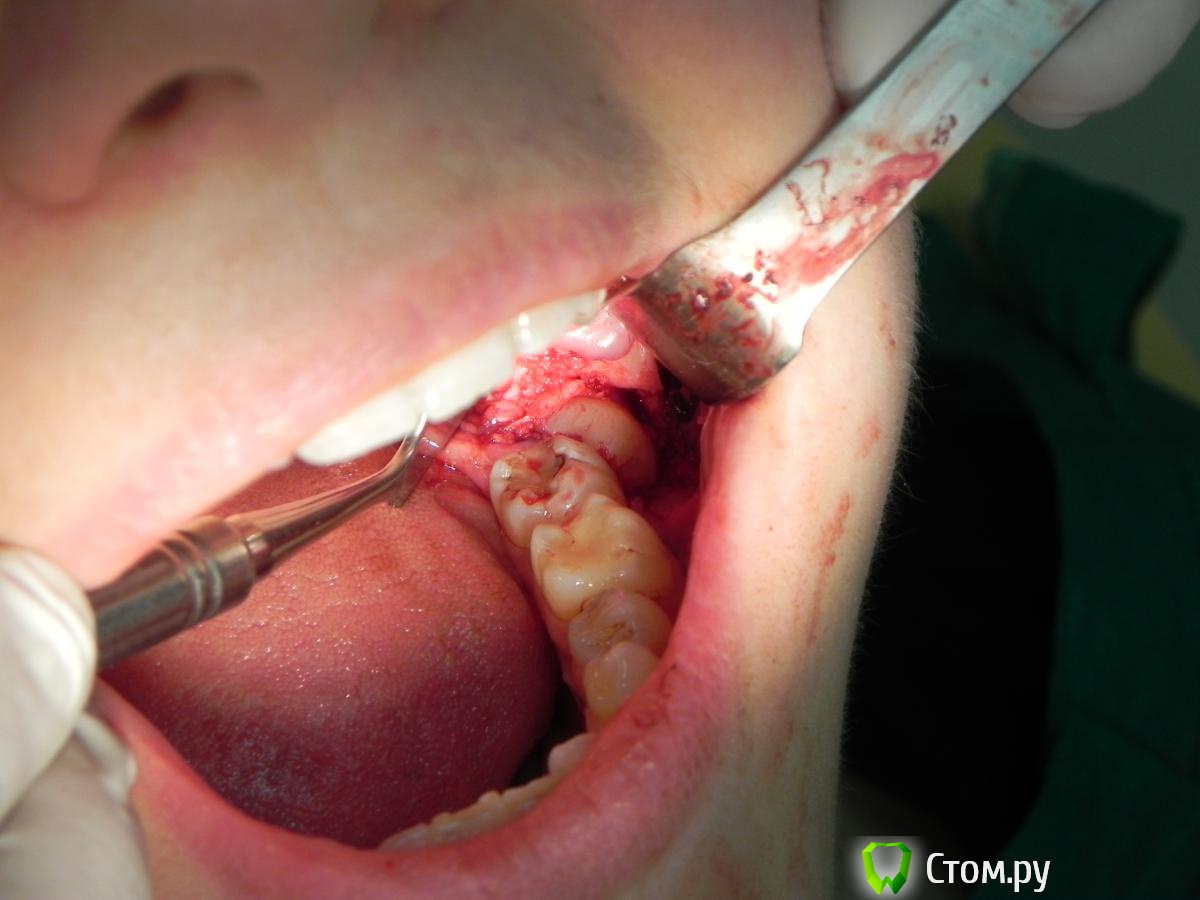

Kostoprav Опубликовано 10 июня, 2014 Поделиться Опубликовано 10 июня, 2014 вот такой клад откопал недавно) 2 Ссылка на комментарий

red_butler Опубликовано 11 июня, 2014 Поделиться Опубликовано 11 июня, 2014 вот такой клад откопал недавно) Почему зуб не сегментировали? 1 Ссылка на комментарий

Kostoprav Опубликовано 11 июня, 2014 Поделиться Опубликовано 11 июня, 2014 (изменено) Почему зуб не сегментировали?Стараюсь не сегментировать дабы рану не засорять "зубным мусором" + наблюдал случаи когда не хилые эмфиземы надували. Хотя бывало приходилось прибегать к этому методу ) Изменено 11 июня, 2014 пользователем Kostoprav Ссылка на комментарий

АнтонТЛТ Опубликовано 11 июня, 2014 Поделиться Опубликовано 11 июня, 2014 Стараюсь не сегментировать дабы рану не засорять "зубным мусором" + наблюдал случаи когда не хилые эмфиземы надували. Хотя бывало приходилось прибегать к этому методу ) Зубной мусор без проблем вмывается, да и эмфиземы не будет если работать с водно-воздушным охлаждением. 2 Ссылка на комментарий

red_butler Опубликовано 11 июня, 2014 Поделиться Опубликовано 11 июня, 2014 Стараюсь не сегментировать дабы рану не засорять "зубным мусором" + наблюдал случаи когда не хилые эмфиземы надували. Хотя бывало приходилось прибегать к этому методу ) Зря, для уборки мусора есть ассистент со слюноотсосом. Эмфаземы боитесь, можно работать микромотором. 1 Ссылка на комментарий

Alexey Doc Опубликовано 11 июня, 2014 Поделиться Опубликовано 11 июня, 2014 а чем minnesota лучше чем ретрактор Фарабефа? а насчет работы микромотором жаль фрез дорогих об эмаль зуба убивать, уж лучше мягкой косточки убрать побольше) я считаю что лучше сегментировать зуб, чем убирать всю мешающую удалению зуба костную ткань - травматизм ниже! Да и не всегда достаточно убрать только кость! пилю турбиной самыми дешевыми алмазными борами ( разовыми так сказать ) - ни одного случая с эмфиземой не было. Ссылка на комментарий